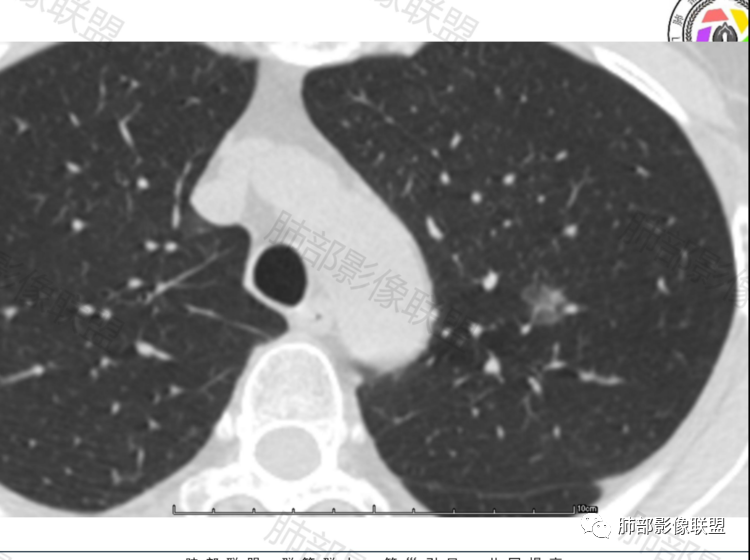

晨读,病例一:左肺磨玻璃结节,边缘清楚,内部有血管穿行自然,有低密度空泡?支气管?10个月后复查,结节增大0.2CM,不排除误差,考虑良性结节或炎性结节,继续短期随访。

病历二:左肺磨玻璃结节影,边界清楚,内部血管穿行,考虑炎性结节或良性结节,继续短期随访。

病例一中年男性,左肺上叶纯磨玻璃结节,边界稍清,内部血管增粗,考虑炎性结节或AIS,建议抗炎治疗后三个月随访。

病例二老年女性,左肺上叶纯磨玻璃结节,边缘清楚,有月牙铲?内部有稍高密度影,血管增粗,考虑微浸润癌MIA,建议密切随访,一个月复查。

病例一:中年男性,左上肺纯磨玻璃结节,边界清,无明显分叶,病灶内见血管穿行,血管隐约稍移位,内部隐约见小空泡,10个月复查 ,GGO持续存在稍稍增大,考虑AIS可能性大,建议继续随访(3个月)。

病例二:中年女性,左上肺亚实性GGO,纯ggo为主,局部见少些条片状高密度实性区,,边界清,有分叶和月牙铲,血管从边缘穿过,14个月后稍有增大,考虑MIA可能,建议手术。

这两个病例都是偶发肺内孤立结节,以磨玻璃密度为主,无明显实性成分,边界清晰,并且都经过长期(10-14个月)随访复查,病灶整体大小、形态、密度变化不明显。

两例最终都选择了手术,病例1结果:局灶性肺纤维化;病例2结果:浸润性肺腺癌。

由此可见,随访持续存在的磨玻璃结节,并不一定都是早期肺腺癌(AIS MIA IAC)或癌前病变(AAH),也可以是局灶性肺纤维化或机化。影像学表现缺乏特异性,有时候并不能完全鉴别。